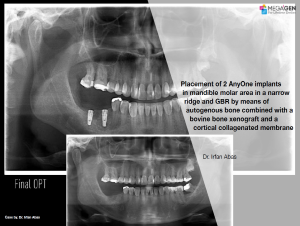

Dr. Achraf Souayah,Edentulous,Aesthetic zone,Maxillary Anterior,Maxillary Posterior,Mandibular Anterior,Mandibular Posterior,Guided surgery,Sinus Elevation,Immediate Placement,AnyRidge,Overdenture system,Meg-Rhein,MILA Kit,Clinical case